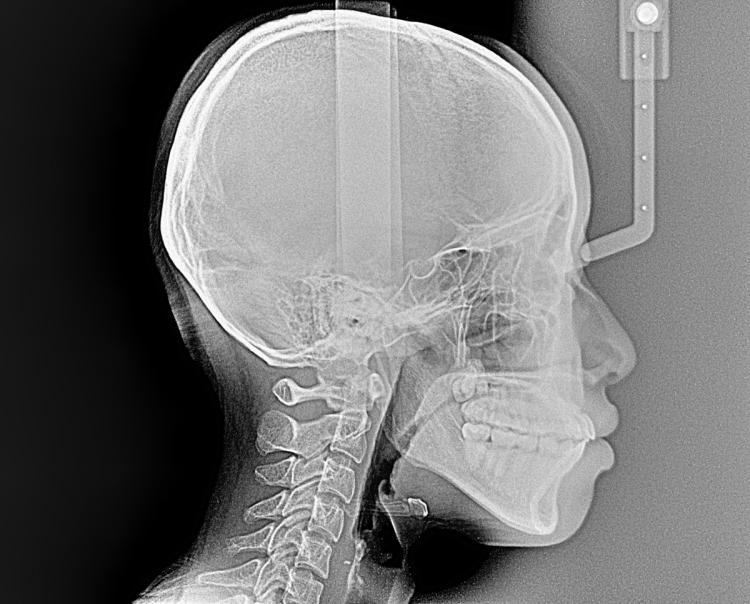

↑今回も矯正診断で必要なレントゲンの1つを紹介します。

矯正診断で必要なレントゲン画像は全部で3つあり、この上の画像はセファロ(側方)と呼ばれるものです。

骨格や前歯の傾きや咬合の状態を確認することができます。